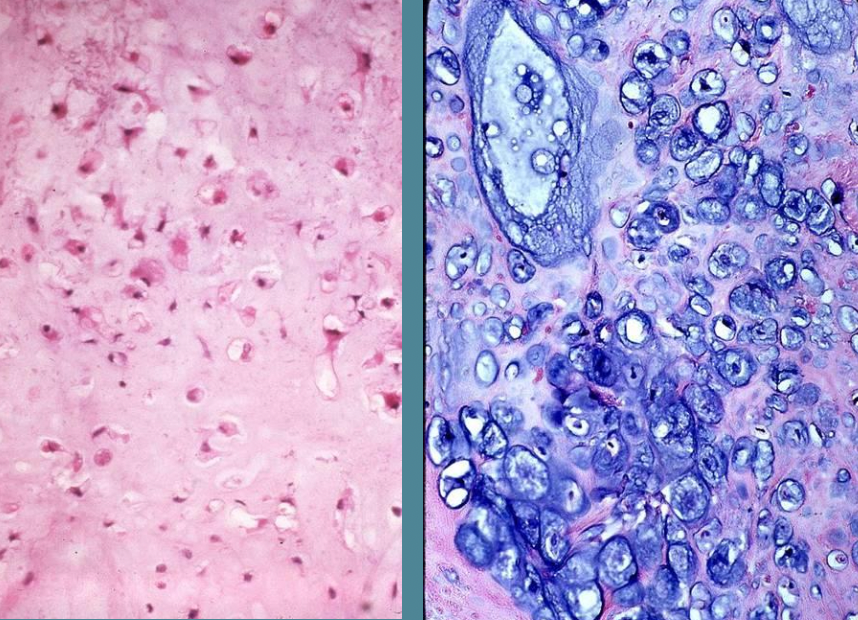

A

Chondrosarcoma, low grade on left, high grade on right